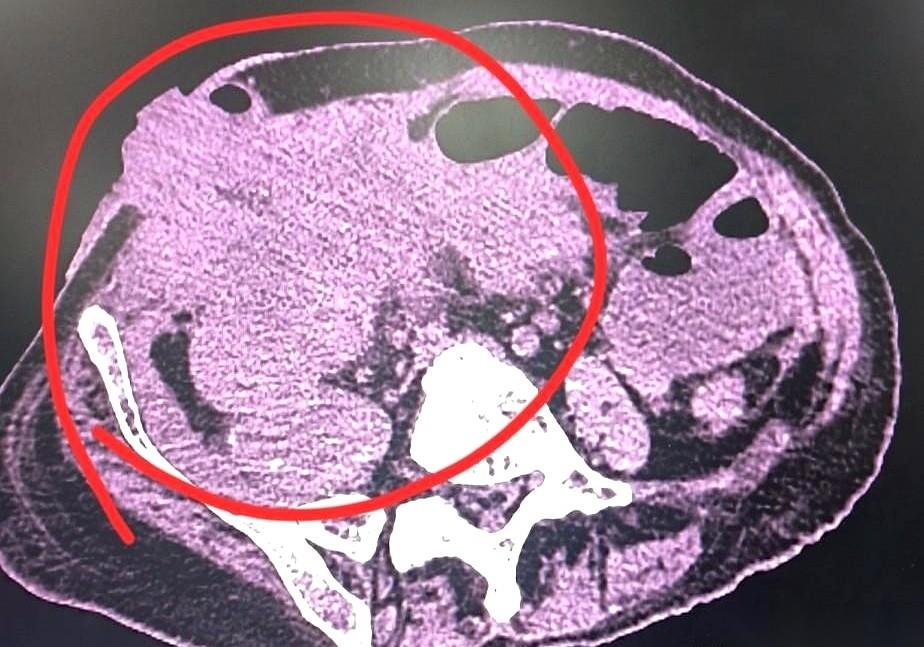

半年,手术白做了。 人又送回来了,肚子疼得不行,造的瘘口也堵死了,根本排泄不出来。 CT一扫,好家伙。 腹腔里密密麻麻全是转移,连骨头都没放过。 其实,半年前手术台上就发现了。 当时就跟家属说,意义不大,已经转移了。 但家属坚持,说哪怕有一线希望也要试。 我们能怎么办?做呗。 手术很“成功”,肿瘤切得干干净净。 结果呢? 老人遭了那么大罪,换来不到半年的安生日子,最后在更大的痛苦里复发。 我有时候真的想跟家属们说句掏心窝子的话: 我们以为的“不放弃”,对病人来说,可能只是“不放过”。 医疗不是神话,医生也不是神。 我们能切掉肿瘤,但我们切不掉规律。 最后的日子,是让他体面、安详地走,还是在无休止的“治疗”里被耗尽所有力气…… 这道选择题,比手术难做多了。 哎。